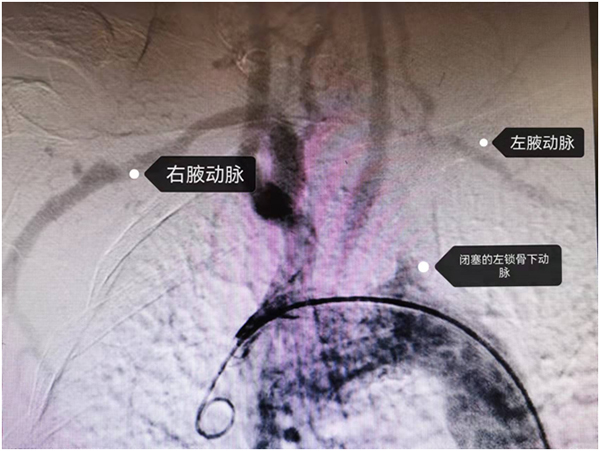

65岁的陈老伯因头晕在我院神经内科住院检查,医生一测血压,发现患者左胳膊的血压明显低于右胳膊,颈部血管彩超检查提示其左锁骨下动脉闭塞,不仅如此,左胳膊还从供应脑子的左椎动脉“窃血”,导致小脑缺血,左锁骨下动脉狭窄就是陈老伯头晕的罪魁祸首。医生了解到,该患者此前曾经在外院做过2次血管内支架植入术,试图开通闭塞的血管,但都没有成功。

为了解除患者的病痛,我院神经内科开展了多学科联合诊疗,考虑到患者左锁骨下动脉闭塞重,介入开通失败,若再次实施介入手术极有可能出现夹层加重,加重病情。血管外科霍鑫主任医师会诊后建议,可实施腋动脉-腋动脉搭桥手术,就是把血压高的右上肢血流引流到血压低的左上肢,从而解决左上肢的缺血症状。手术只需在双侧肩部各开一个5cm切口,再用人工血管通过胸部皮下隧道与双侧腋动脉相吻合即可,创伤小,恢复快。